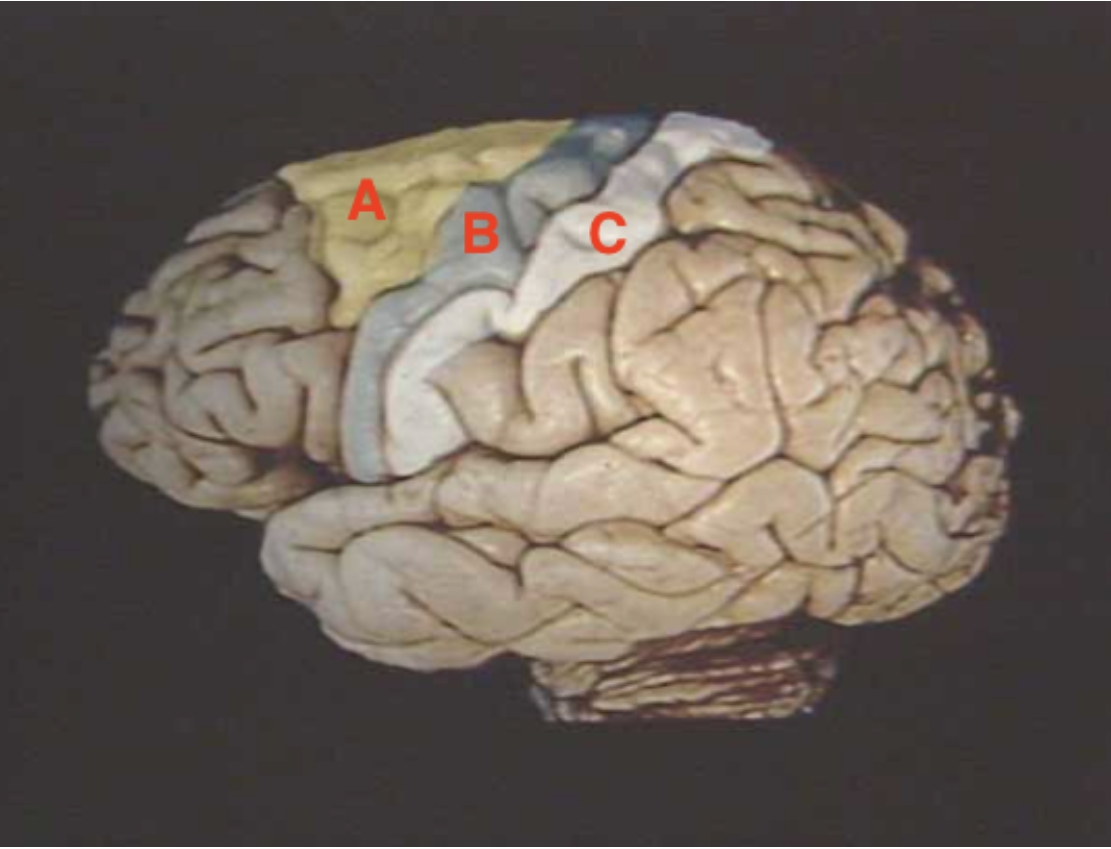

A

Premotor Cortex

B

Precentral Gyrus

C

Postcentral Cyrus